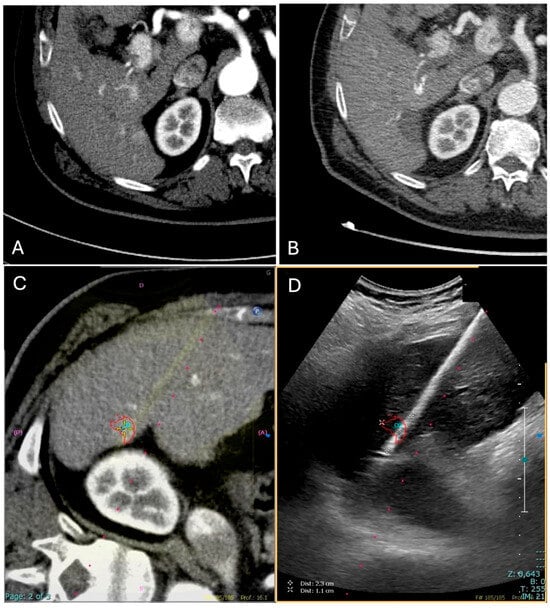

Once the microwave 13.5 G antenna (Emprint Microwave Ablation System, Medtronic, and Covidien, Boulder, CO, USA) was in place, sedation was deepened and ablation was performed with a power of either 100 or 150 W for a time established by the operator based on the tumor size and the microwave manufacturer data; all cases were ended with track ablation (Figure 2).

Figure 2. Contrast-enhanced CT (CECT) in the arterial phase demonstrates a newly diagnosed HCC located in segment VI of the liver, near the hepatic capsule. (A) The lesion shows intense arterial-phase hyperenhancement (wash-in), a typical imaging hallmark of HCC. (B) One-month follow-up CECT shows no residual enhancement, consistent with complete response to treatment. (C) CT–US fusion image following co-registration, enabling precise visualization of the lesion (highlighted by a red target). (D) The corresponding real-time US image during the ablation procedure, with the lesion and ablation needle clearly visualized (highlighted by a red target).